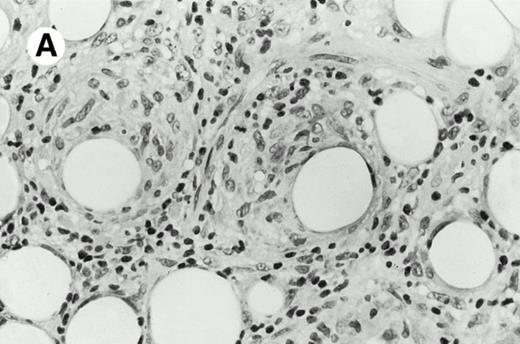

Three cases (cases no. 1 to 3) were located in the nasal cavity. The neoplastic infiltrate consisted of medium and/or large pleomorphic lymphoid cells (Fig 1)intermingled with variable numbers of small lymphoid cells, plasma cells, eosinophils, and histiocytes. Features of angiocentrism and angioinvasion, epitheliotropism, and areas of necrosis were observed in all three cases. Patient no. 4 presented with disease restricted to the lung and an open-lung biopsy was available. The neoplastic infiltrate was composed of large atypical lymphoid cells and was predominantly interstitial without extensive destruction of the normal architecture. Features of angiocentrism, angioinvasion, and epitheliotropism were present (Fig 2A and B). Case no. 5 involved the larynx, extending to the piriform sinus, the ventricle, and the arytenoid. One month later, the lymphoma disseminated to the subcutaneous tissue in the spinal region and biopsy specimens from both sites were available. The neoplastic cells were medium and large, with abundant clear cytoplasm and slightly irregular nuclei with dense chromatin. Epitheliotropism was present in the larynx mucosa. Small foci of necrosis and angiocentrism were seen without angioinvasion. Three patients presented with cutaneous disease. Cases no. 6 and 7 were comparable, as both histories started with necrotic subcutaneous nodules of the thigh, which on histologic analysis were characteristic of cytophagic histiocytic panniculitis without evidence of lymphoma (Fig 3A). Second excisional biopsies of cutaneous nodules obtained 7 and 5 months later, respectively, showed characteristic features of lymphoma in both cases (Fig 3B). However, in case no. 6, skin biopsy specimens showed an epidermotropic PML lymphoma extending to the dermis and the subcutaneous tissue, whereas in case no. 7, the neoplastic infiltrate consisted of a PSC confined to the subcutaneous tissue, admixed with benign histiocytes that showed phagocytosis. Patient no. 8 presented with recurrent skin lesions with spontaneous remission over a period of 10 years. The initial skin biopsies demonstrated an intense epidermotropic neoplastic infiltrate that extended to the superficial and deep dermis composed of atypical PML cells. All cutaneous cases displayed features of angiocentrism, but angioinvasion was observed only in case no. 6 and foci of necrosis in cases no. 6 and 8.

Pleomorphic large-cell γδ T-cell lymphoma (case no. 3) (nasal biopsy specimen with hematoxylin-eosin stain).

Pleomorphic large-cell γδ T-cell lymphoma (case no. 3) (nasal biopsy specimen with hematoxylin-eosin stain).